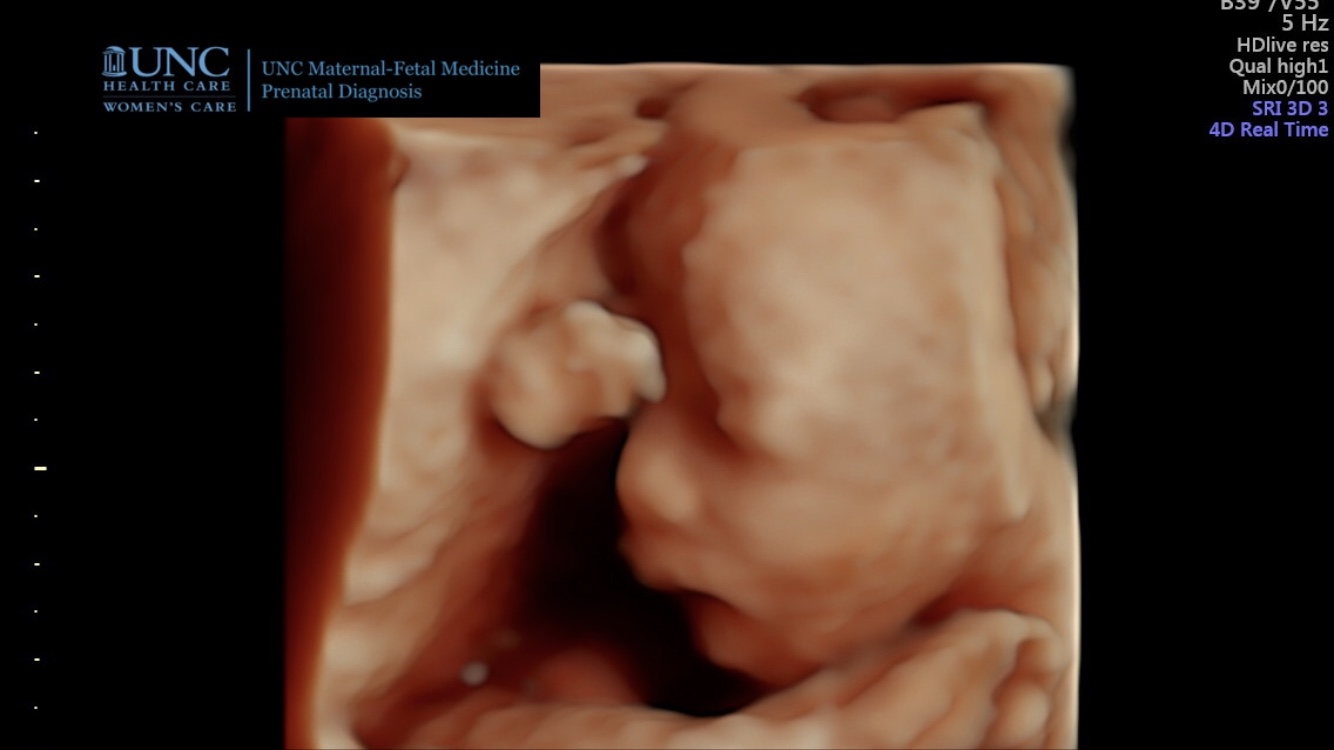

On Thursday February 21 we had our normal prenatal appointment. We heard her heart beating at a strong 147 bpm. The midwife brought out a small ultrasound machine to determine her position. She was head down! That was a relief to me. The midwife measured my belly. I was supposed to be 34 cm but was 31 cm. She ordered a growth scan for Monday to ensure Ginny was growing properly. She said that most likely everything is fine and she is growing, but we want to just make sure since my belly was small. This made me a little nervous but also excited. I was glad we would get another chance to see her before she was born.

I looked forward to the ultrasound on Monday afternoon. I tried not to get my hopes up that we would get a good face picture. I knew she was pretty squished in there so it might be hard to get one. I was so eager to see her.